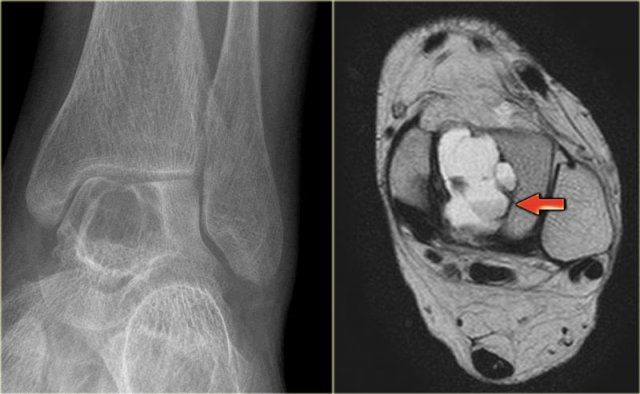

ABC in talus ABC in talus

ABC (5)

On the left an expansile well-defined osteolytic lesion with a sclerotic margin in the talus.

Axial PD-weighted image shows lobulated contours and cystic appearance with fluid-fluid level (arrow).

Most likely diagnosis: ABC.

Differential diagnosis:

chondroblastoma with secondary ABC.